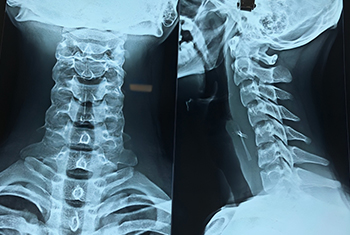

Advanced treatment for nasal blockage, sinus disease, allergies and watery eyes with Endoscopic Sinus Surgery, Septoplasty, Rhinoplasty, Dacryocystorhinostomy and Endoscopic DCR.